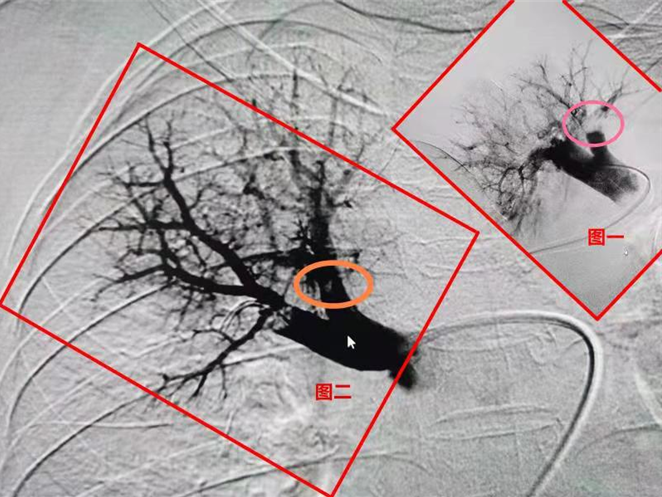

在武汉市肺科医院放射科血管介入室,主治医师李晟医生发现,魏婆婆的肺动脉上全是成块的血栓淤积,肺动脉险些被这些突如其来的血栓堵死(若完全堵死可以瞬间致命)。

李晟与同事配合,通过股静脉将血管介入治疗设备送抵魏婆婆的肺动脉,在这里他们将血栓溶解、打碎再抽吸出来。

为了防止下肢深静脉继续「发射」血栓过来,李晟还在下腔静脉的回心总路植入一个滤网,拦截血栓。